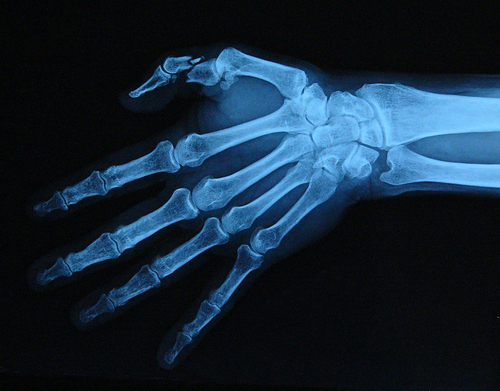

A team of doctors from Jaypee Hospital have successfully performed a complex surgery on an Afghan national whose toe was transplanted to reconstruct a thumb, the medical institute said on Tuesday.

Irfaan-ul-lah, 22, had lost his three fingers and thumb in a bomb blast two years back and was left with only an index finger in his right hand.In a seven hours 'Toe Transplant for Thumb Reconstruction' surgery, the doctors successfully transplanted a toe to reconstruct a thumb in the right hand. In the first stage, the patient's hand was assessed to find out to what extent the loss of structures such as bones, joints, tendons, arteries and veins have happened. Then, the team decided to implant the second toe of his left foot to his right hand, giving it a structure of a thumb.